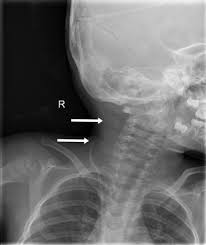

Lateral Skull X Ray Confirming A Ventricular Shunt Including The Download Scientific Diagram

Vp shunt valve x ray. Most pediatric patients with hydrocephalus are treated with ventriculoperitoneal vp shunt placement. Programmable cerebrospinal shunts are a type of ventriculoperitoneal shunt that can be set to different csf pressure settings. Usually a simple lateral skull x ray helps to identify the type of valve and it s adjustment.

Indications departmental protocols will vary but the overall goal is to image the shunt in its entirety to assess. Shunt obstructions may be confirmed with radioisotope examination or with fluoroscopically guided injection of iodinated contrast material into the shunt reservoir. The verification of shunt adjustment so called opening pressure and also the primary identification of the implanted valve type can be a problem in daily practice.